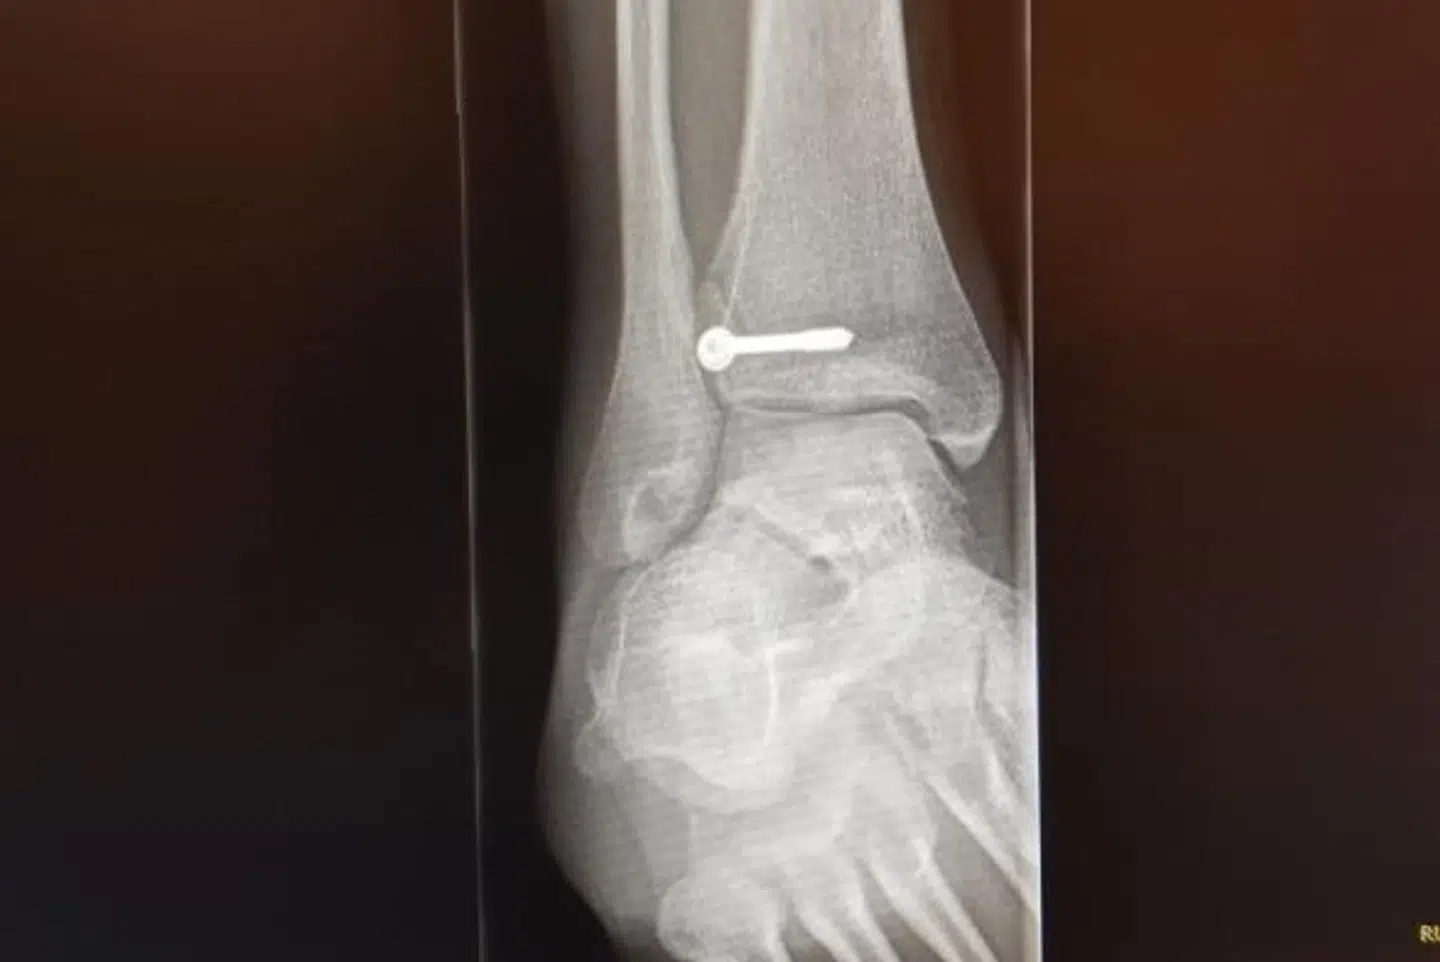

Et par dage efter ventede der ham dog en nedslående melding. Benet var brækket, viste undersøgelsen, og derfor var en operation uundgåelig.